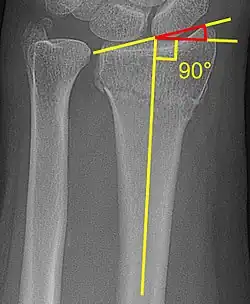

Radial inclination

The radial inclination of a distal radius fracture is shown in red in image at right. The angle is measured between:[5][6]

1. A line drawn between the distal ends of the articular surface of the radius on an AP view of the wrist.

2. A line that is perpendicular to the diaphysis of the radius.

Radial inclination is normally 21-25°.[7]